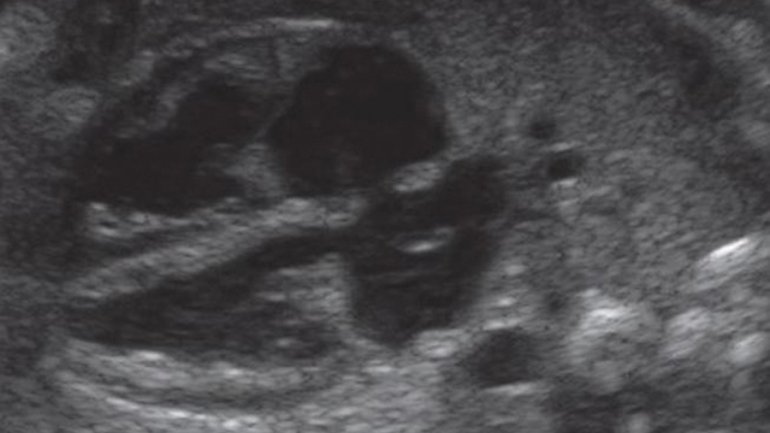

Ultraschall 4. SSW

In der 4. Schwangerschaftswoche nistet sich die befruchtete Eizelle in der Gebärmutter ein. In dieser Phase der Frühschwangerschaft ist nur die Fruchthöhle (schwarz) zu sehen, da der Embryo noch zu klein ist. Das restliche Bild zeigt die gut aufgebaute Gebärmutterschleimhaut (Endometrium), in der sich die Eizelle einnisten kann.